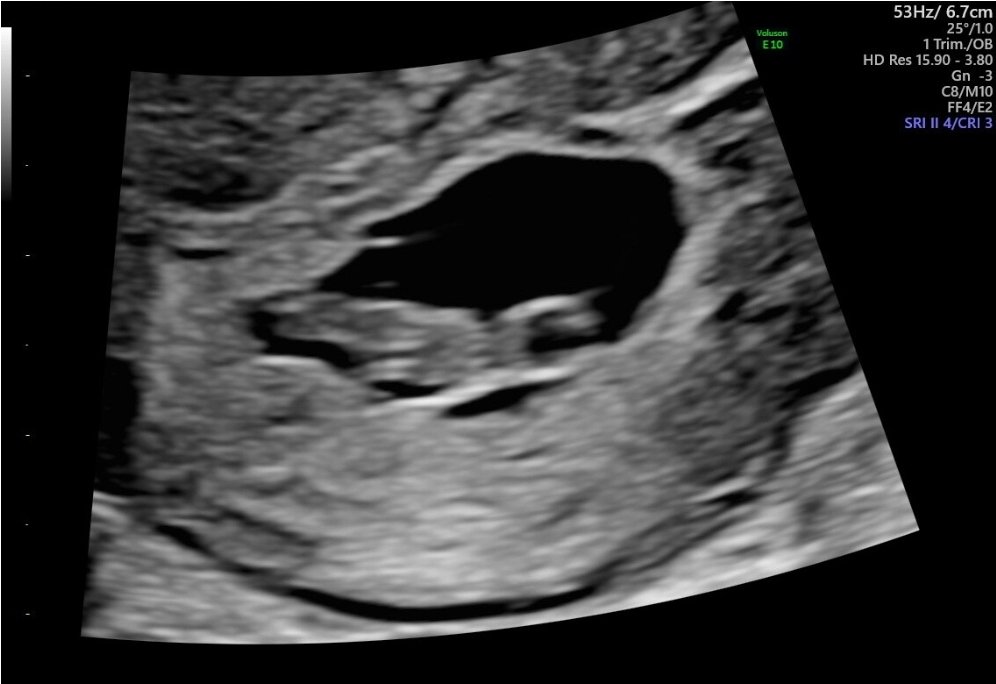

Gravid 7+5 og første ultralyd

det er bare én inni her, den ble målt til 7+3, men tror jeg står ved min utregning til otul. Det blir så mange apper å endre på hver gang

Fikk video tilsendt av hjertet som slår, kommer til å se mye på den ja

Hun tok utvendig ul, faktisk.

Skjønneste lille